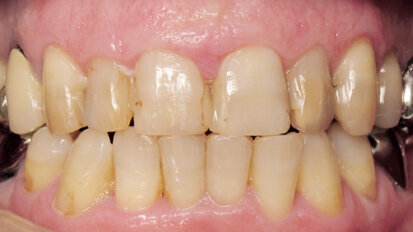

Nový úsměv za jeden den

Čt. 28. května 2020